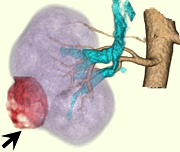

術前CT精査の例(腎細胞癌)

術前精査では、組織診断を推定するための造影 dynamic study(図1-4)と体幹部を含めたスキャンによる病期診断、また、手術シュミレーションに活用できる立体像(図5,6)作成を行っています。

| 図5 造影CT再構成A 右腎動脈は太い枝と細い枝と2本存在する |

図6 造影CT再構成B 動脈(橙色)、静脈(水色)、腎臓(紫色)、病変(赤)で立体的に表示 |